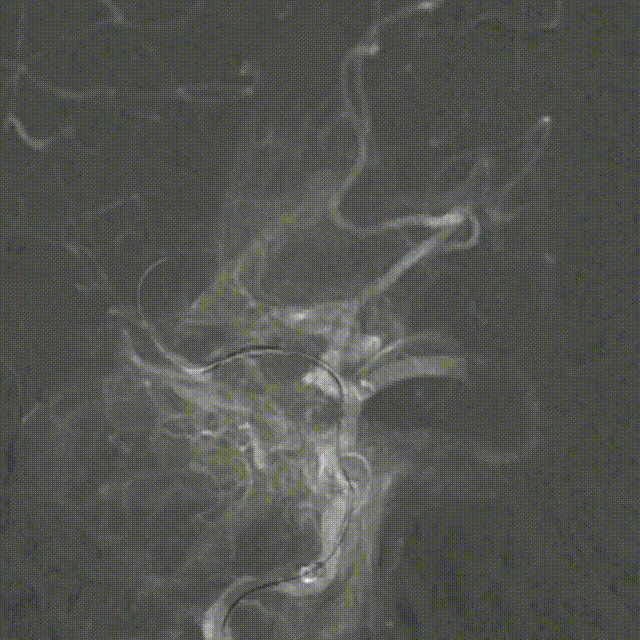

球扩后造影:狭窄明显改善,前向血流明显好转,未见血栓征象,球囊部分回收支架,撤出。

观察15min,未见弹性回缩,正侧位造影。

Syphonet®取栓支架释放后可根据支架的蜂腰形态定位血栓位置。且与血栓融合过程,全程可视,支架直径压缩程度的改变可反馈支架与血栓的融合过程。回撤支架,观察血栓是否移位。